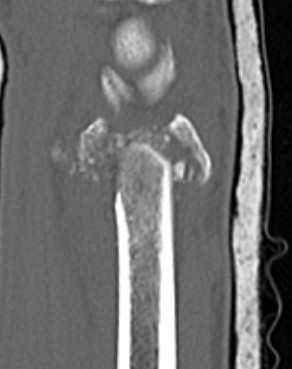

Dorsal distraction plating

Indication

Internal radiocarpal distraction

- unreconstructable distal radius fractures

- early weight bearing in poly trauma patients

- osteoporotic bone

Advantage - no pin site infection from external fixation

Disadvantage - need to remove plate at 3 - 4 months once fracture united

Technique

Extended dorsal approach

- protect sensory radial nerve

- open 3rd extensor compartment / retract EPL radially

- mobilized 4th extensor compartment / retract EDC ulnarly

- bare area of radius proximally between EDC and ECRB / ECRL

Fixation to 2nd or 3rd metacarpal first

- 2nd metacarpal: under 2nd extensor compartment

- 3rd metacarpal: under 4th extensor compartment

- reduce / distract joint

- +/- additional radius fixation